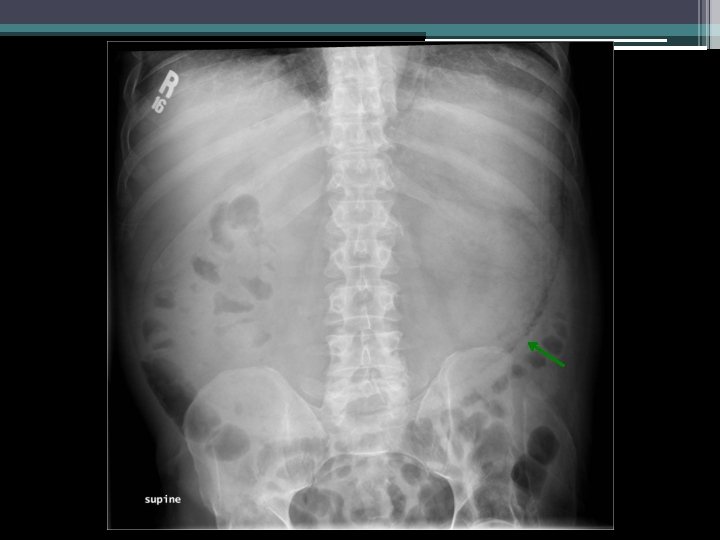

Imaging

Clinical course • • Return of nausea and vomiting NG tube decompression: >3 L nonbloody output Saline load test markedly positive Repeat KUB

Gastric emphysema • Diagnosis: gastric emphysema due to gastric outlet obstruction • Pneumatosis intestinalis ▫ Gastric pneumatosis Gastric emphysema Emphysematous gastritis ▫ Pneumatosis coli